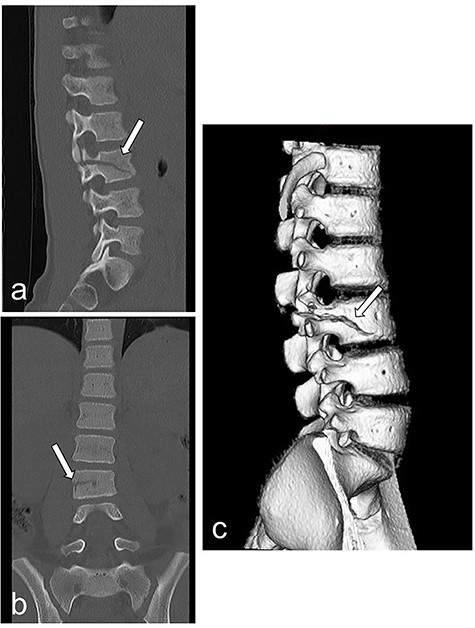

A 10-year-old girl was sitting in the back seat of a right-hand drive car, behind the driver, when another car came from the front and bumped into the patient’s car on the right side. The patient was restrained in a three-point seat belt (shoulder and lap belts). She was transferred to our hospital, where she was alert and communicative on arrival. Her chief complaint was abdominal pain. She was 137-cm tall and weighed 30 kg. On presentation, her heart rate was 87 beats/min, her blood pressure was 123/62 mm Hg, her respiratory rate was 20 breaths per minute, her oxygen saturation was 100% and her temperature was 36.7°C. A seat belt sign was observed, with contusions on the forehead and the right iliac region. Her abdomen was tender and she displayed guarding. Focused assessment with ultrasonography for trauma showed a fluid collection in the pelvic cavity. Enhanced computed tomography (CT) demonstrated no free air but confirmed the presence of a fluid collection in the pelvic cavity (Fig. 1a and b). Radiography and CT showed a fracture of the lumbar spine at L3 (Fig. 2a–c).

Radiography and CT on hospital day 1. (a, b) Radiography shows fracture of the lumbar spine at L3. (c) CT shows a fracture of the lumbar spine at L3.